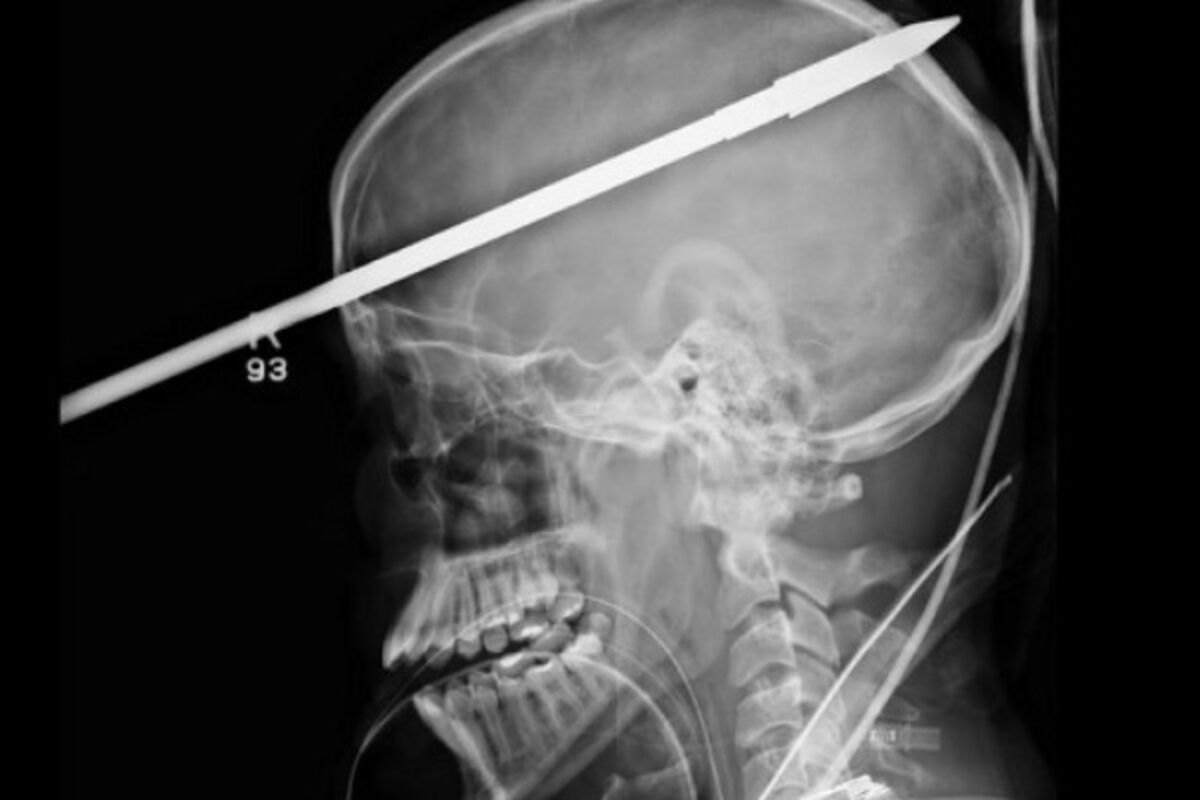

Strijela u glavu, Foto: Telegraph.co.uk

Američki tinejdžer Jaser Lopez preživio je harpun u glavi. Lopez je sebi slučajno ispalio harpun u glavu, a udar je bio toliko jak da ga je oborio u jezero na kojem je pecao sa drugom.

Lopez je hitno prebačen u bolnicu u Majamiju gdje su doktori morali odsjeći dio strijele da bi mogali da mu skeniraju glavu, piše britanski Telegraf.

Čudom, harpun je prošaotik pored njegovog desnog oka i zarila se u lobanju probivši desnu stranu njegovog mozga.

Doktor koji ga je operisao kazao je da je Jaser imao mnogo sreće jer je harpun promašio svaki veći krvni sud, i nije oštetila lijevu stranu mozga čime bi izgubio govor, a harpun je uklonjen bez oštećenja mozga.